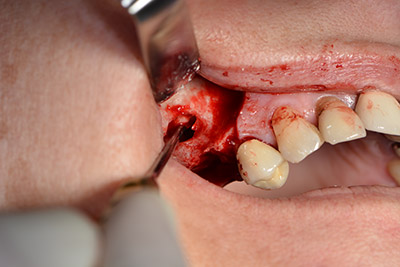

El guiado clásico del corte (crestal, descarga bucal) y la preparación del colgajo mucoperióstico permiten obtener una buena visión global.

La ventana se crea a una velocidad de 35.000 rpm y, a continuación, la membrana de Schneider se prepara en sentido craneal (figuras 13 a 14).